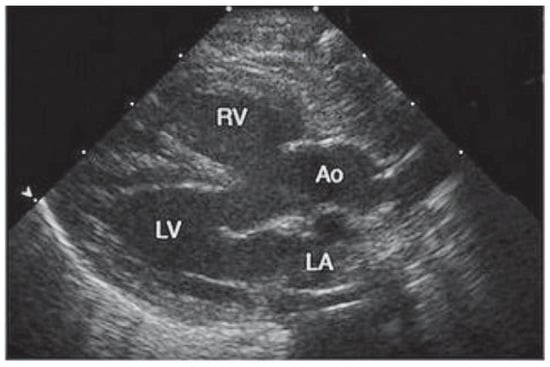

Tetralogy of Fallot, first described by Etienne Fallot [] (Figure 1) in the classic paper “l’anatomie pathologique de la maladie bleue” in 1888, is the most common cyanotic congenital heart defect (6%). It compromises an interventricular septal defect, right ventricular outflow tract obstruction, an overriding aorta, and a right ventricular hypertrophy (Figure 2 and Figure 3).

Figure 3. Echocardiogram with anterior displacement of the outflow ventricular septum that results in stenosis of the subpulmonic right ventricular outflow tract, overriding of the aorta, and an associated ventricular septal defect. (This picture was published in: Nelson Textbook of Pediatrics. Kliegman RM, Behrman RE, Jenson HB, Stanton BF, edts. 18th edition. Oxford: W. B. Saunders; 2007. Copyright © 2009 Elsevier, Oxford, UK.) Ao = overriding aorta; LA = left atrium; LV = left ventricle; RV = right ventricle.